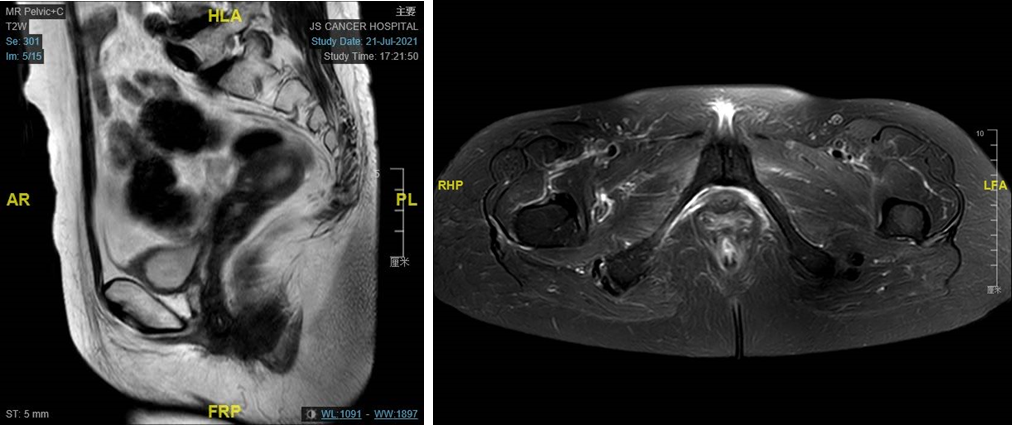

盆腔MRI检查:阴道后壁肿瘤完全消失,宫颈后唇肿瘤完全消失。

图3. 盆腔MRI提示阴道后壁肿瘤消失,宫颈后唇肿瘤消失,内膜完整,宫颈管结构清晰